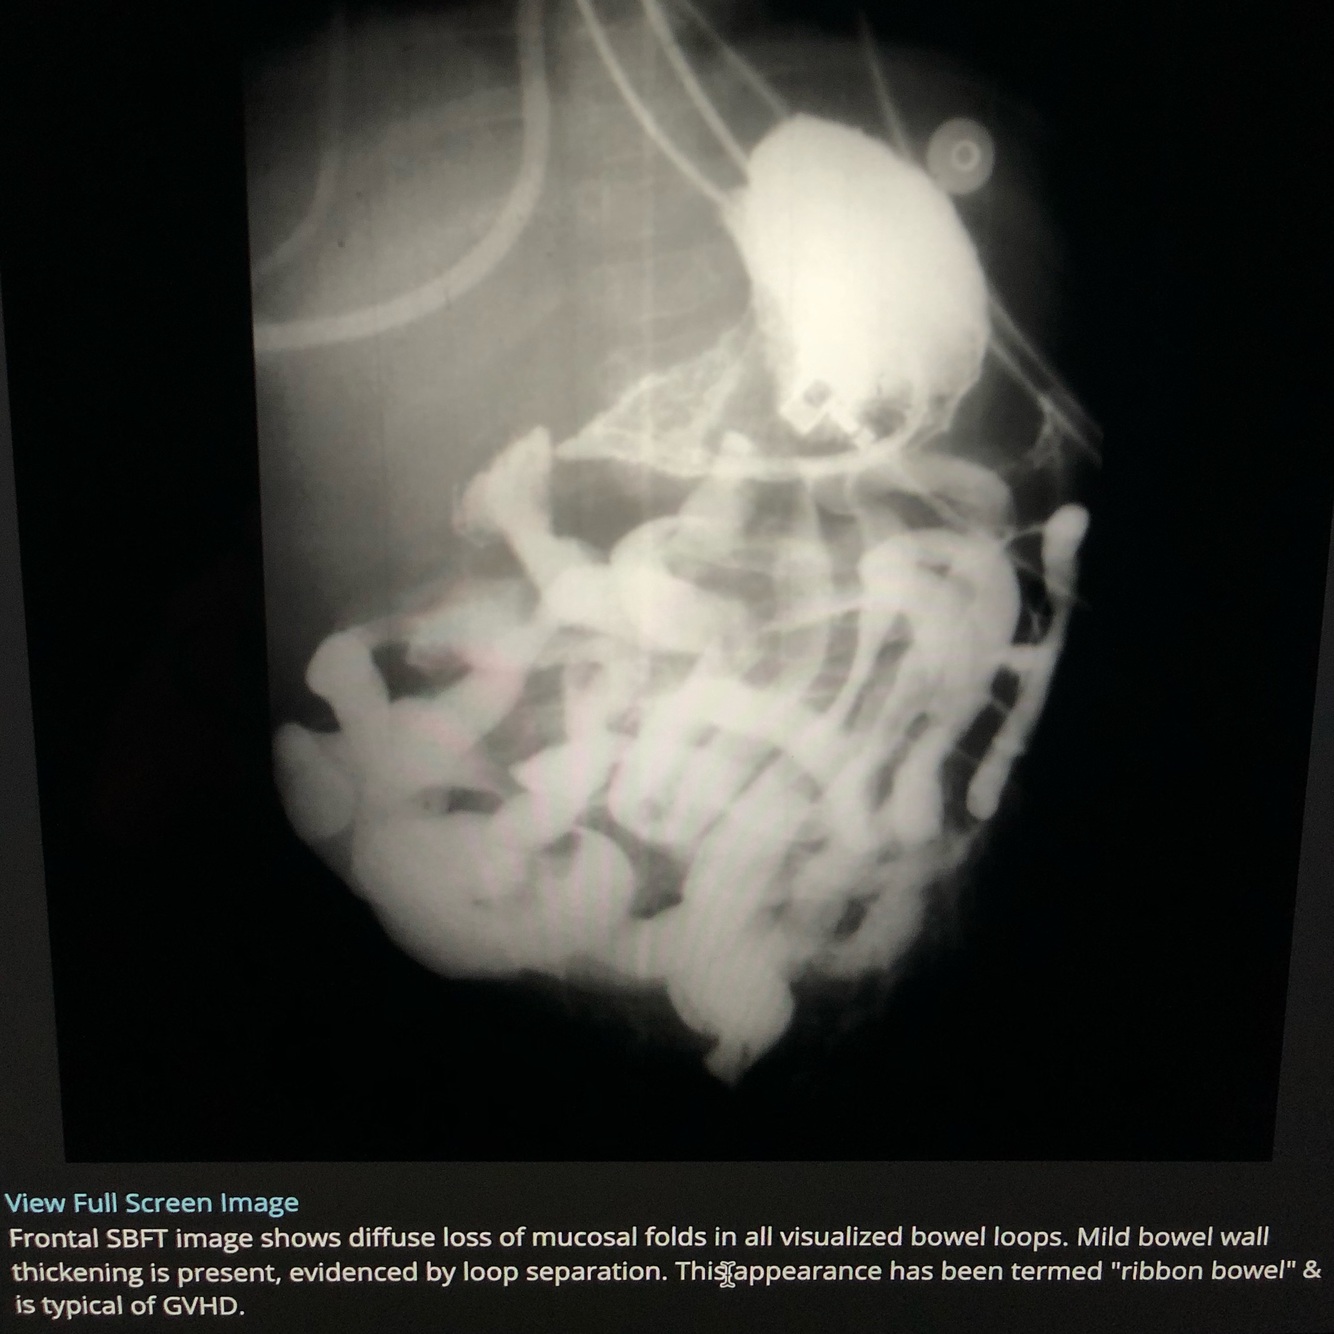

Which of the following is FALSE regarding Graft Versus Host Disease?

Marked luminal narrowing of small bowel results in ‘ribbon like’ appearance on enterography

CCF -Mediated by B lymphocytes of donor graft - FALSE

-mediated by T lymphocytes